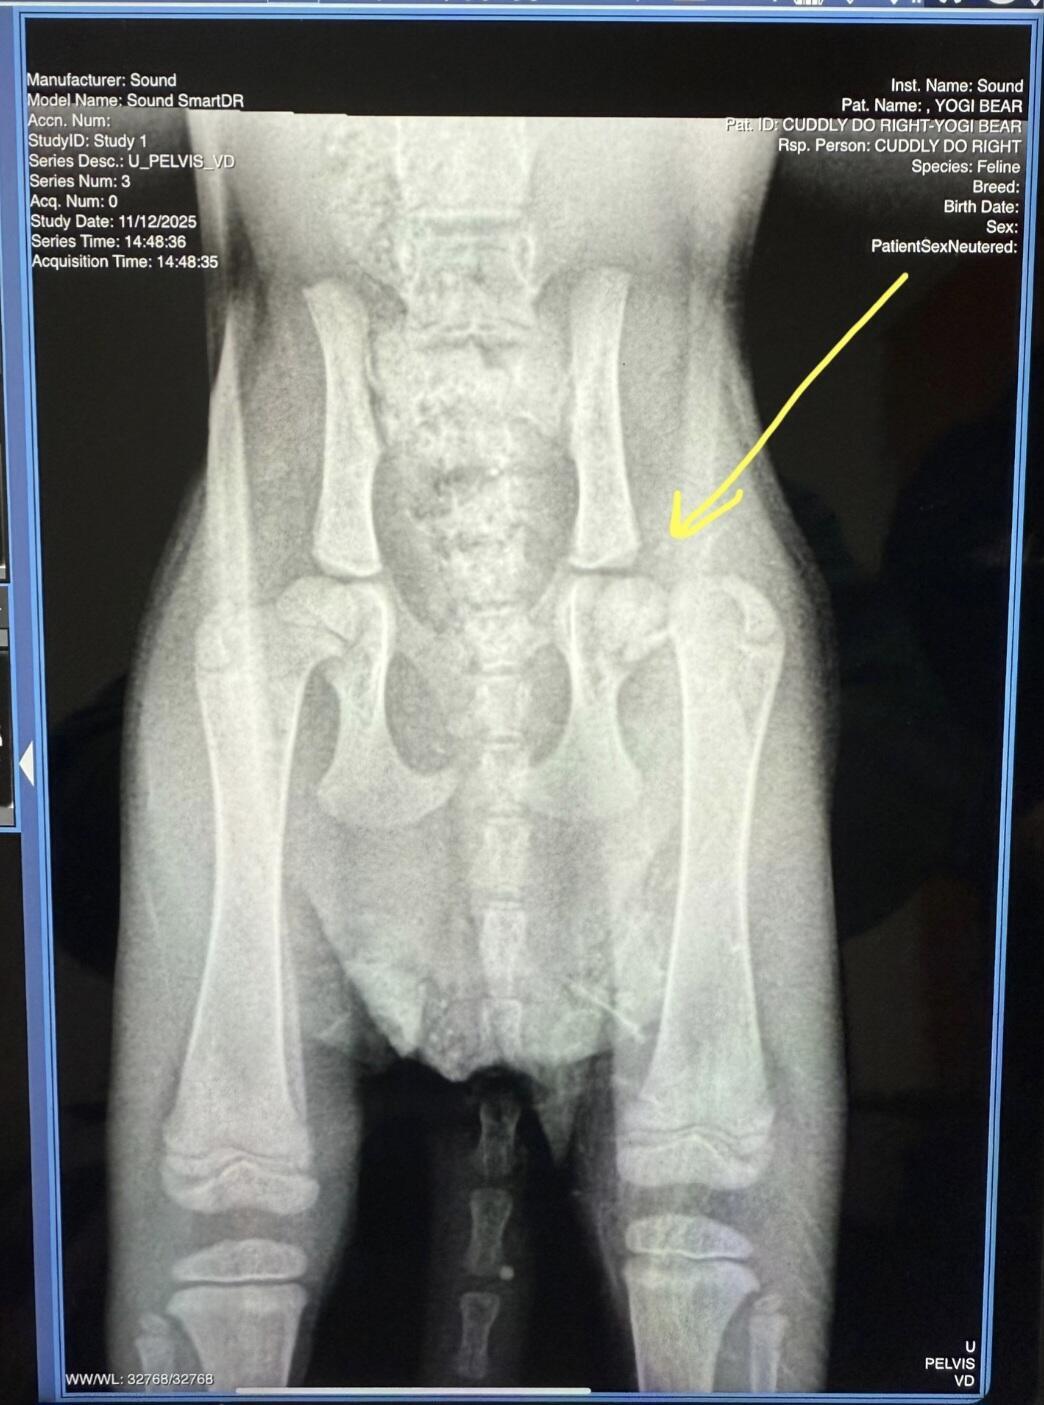

Yogi Bear has a real Boo Boo. Not a sidekick - a fractured femur!

Yogi was found outside on the wintery-cold night of November 11th, hiding in the rim of a car's tire. Less than 24 hours later, her entire life has turned for the better! Except for one thing: she has a fractured and dislocated left femur.

We are fundraising to get her the surgery she needs, the routine vet care every kitten requires and the supplies that will get her through to the end of her recovery. Yogi's initial bill was $385 and the current estimate for her surgery is $1500-1800. The full cost of her care and EIGHT weeks of recovery is not yet known, but we'll keep everyone informed on her web page!